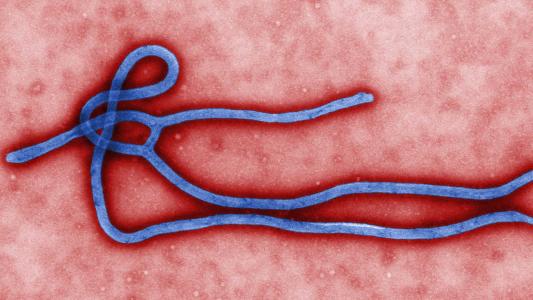

CRISPR can diagnose Zika (and Ebola) with just a strip of paper

We could be on our way to a fast, reliable, portable test for almost any virus or cancerous mutation.

The ebola vaccine is still working 2 years later

The vaccine works great at preventing infection—let’s hope it can also prevent media panic too.